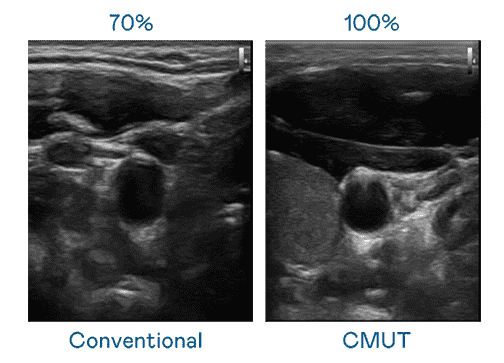

CMUT 技术是一种用电容式微机电元件来产生超音波讯号的技术。。。与传统 PZT 压电式技术相比,,CMUT 频宽增加 30%,,,,更宽频的超音波讯号让影像解析度大幅提升,,,是实现高影像品质医疗超音波扫描、、促进精准医疗发展的关键技术。。。。

大频宽带来超清晰影像

超音波影像的解析度高低,,首先取决于探头能发出的讯号频宽。。尊时凯龙 CMUT 可提供高清晰的超音波讯号,,提供高频宽、、高灵敏度、、影像纹理细节更高的超音波影像,,,协助医护人员缩短影像判读时间及利用精准的医疗影像进行诊断。。